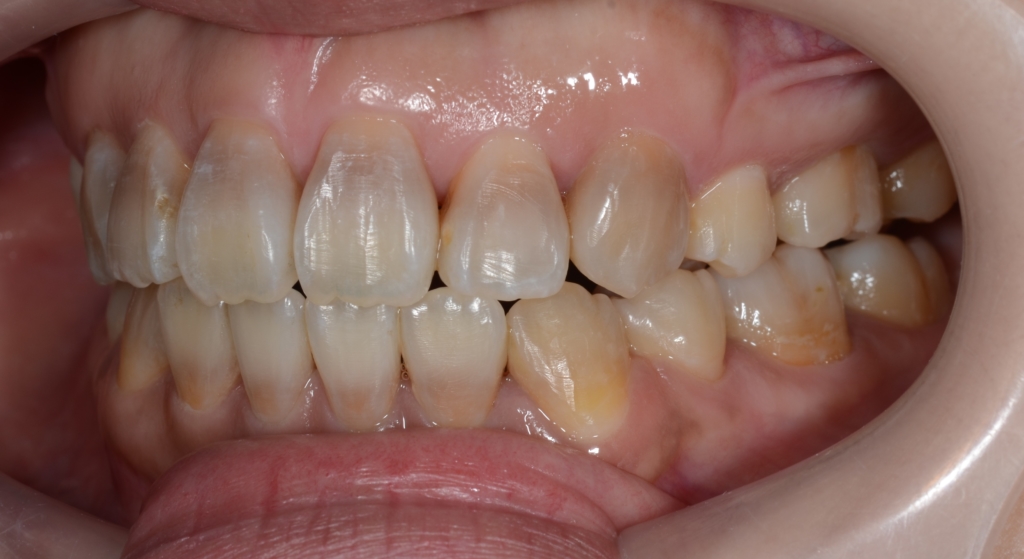

患者さんは、20代の女性(社会人)です。

「八重歯などのガタガタを治してきれいな歯並びになりたい!」

というのが一番の希望でした。

合わせて、口元が少しでも引っ込んで、お口を閉じる時にオトガイ辺りの「力」が抜けてしわが無くなればもっと嬉しい!とのことでした。

#1.顎と歯の不調和による叢生(重度)

#2.上顎前突(出っ歯)

#3.開口

と診断しました。